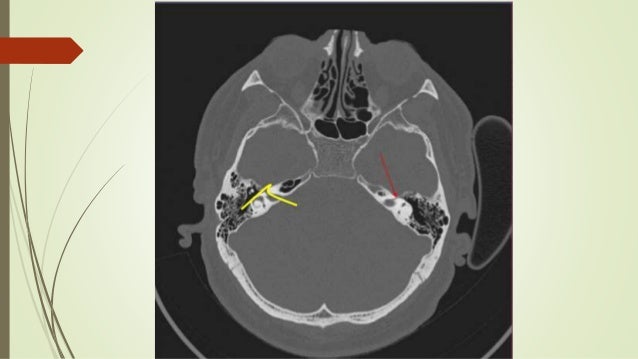

Ct Scan Temporal Bone Dr Zeeshan Ahmad

Ct scan temporal bone Dr Zeeshan Ahmad www.slideshare.net

zeeshan